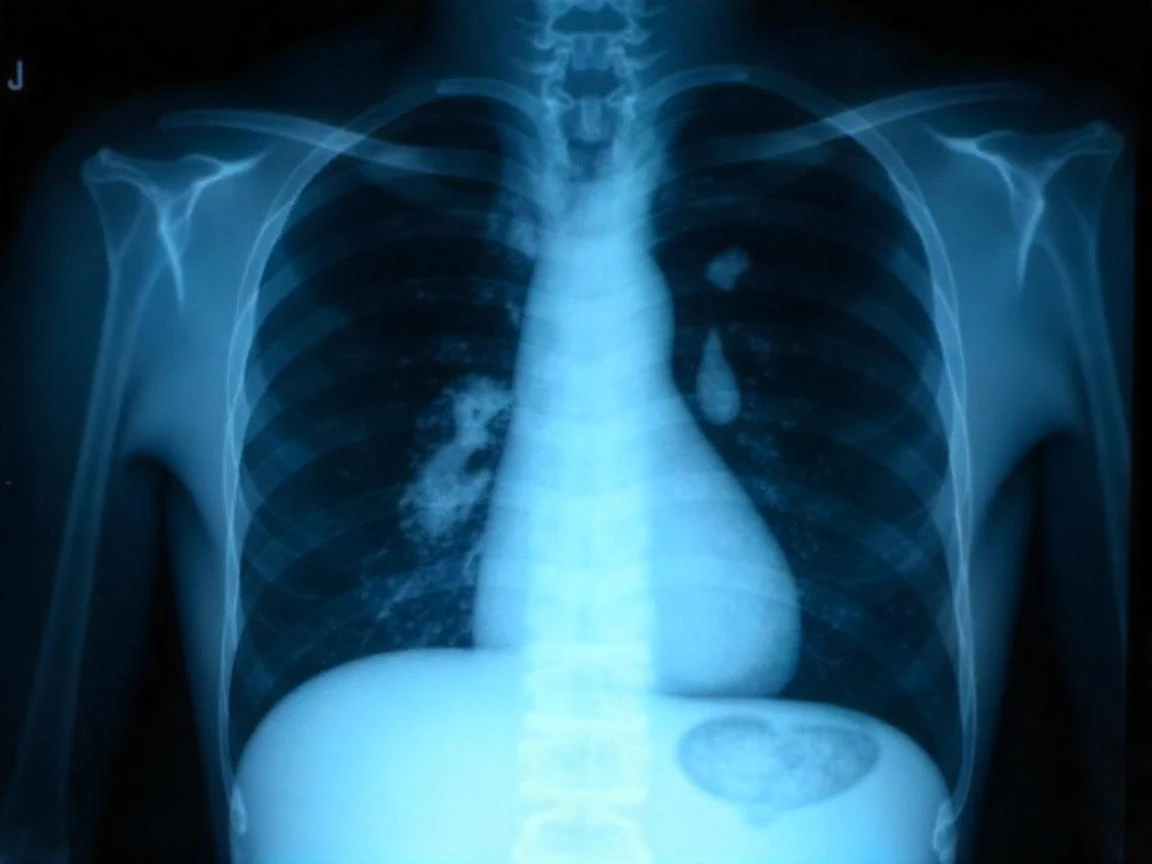

Akciğer kanserinin dünya genelinde ve Türkiye'deki yaygınlığına dikkat çeken Prof. Dr. Öz, sigara kullanımının en büyük risk faktörü olduğunu belirtti. Pasif içicilik, hava kirliliği, asbest ve genetik faktörlerin de akciğer kanseri riskini artırdığını ifade etti. Erkeklerde kadınlara oranla 3,5 kat daha fazla görülen bu hastalığın belirtilerinin göz ardı edilmemesi gerektiğini vurguladı.

Prof. Dr. Öz, geçmeyen öksürük, kanlı balgam, nefes darlığı, hırıltılı solunum, ses kısıklığı gibi solunumla ilgili belirtilerin yanı sıra iştahsızlık, kilo kaybı, kronik yorgunluk, göğüs ağrısı ve tekrarlayan akciğer enfeksiyonlarının da akciğer kanseri işaretleri olabileceğini söyledi. İleri evrelerde ise kemik ağrıları, baş ağrısı ve bilinç değişiklikleri gibi belirtilerin görülebileceğini aktardı.

Akciğer kanseri cerrahisinde uygulanan yöntemler hakkında da bilgi veren Prof. Dr. Öz, lobektomi, pnömonektomi, segmentektomi/wedge rezeksiyon ile minimal invaziv yöntemler olan VATS ve robotik cerrahinin tedavi seçenekleri arasında yer aldığını söyledi. Tedavi sonrası düzenli takibin, sağlıklı beslenmenin, egzersizin, sigarasız yaşamın ve psikolojik desteğin hastalığın tekrarlama riskini azaltarak yaşam kalitesini artırdığını sözlerine ekledi.